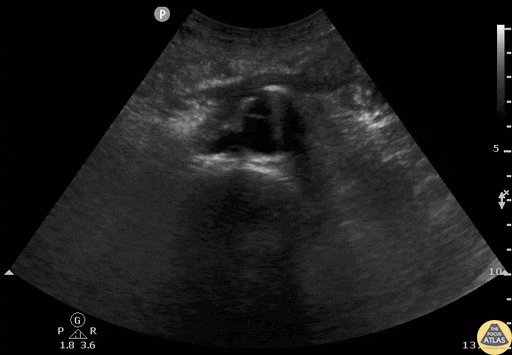

Saccular AAA with Dissection Flap. Contributor: Daniel Ostapowicz, MD